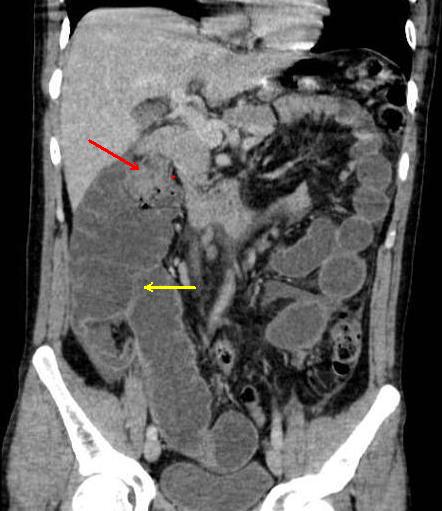

Occlusion du colon a cause

cancer du colon droit . Colon ascedante en amont de

lesion est tres dilate avec imcompetence de la

valvule Bauhin ( fleche jaunne ) .La masse du tumeur

est hyper-dense a bord irregulier (fleche rouge )

situe au colon pres de angle colique droite .

Le colon en aval est collapse . |

|

Meme cas en coupe axiale .

La masse du tumeur est hyper-dense a bord irregulier

( fleche rouge ) situe a la region sous hepatique

droit |